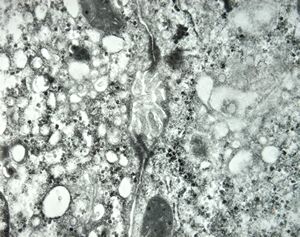

F,45y. | metastasis - carcinoid